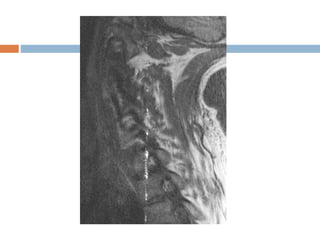

Slice overlapping

 Loss of signal due to multi slice, multi angle

acquisition or imperfect slice profile.

 Mechanism : Spin saturation.

 If slices at different angles cross, then spins that

have previously excited, could be excited again.

 Mostly seen in spine imaging e.g. L4-L5 or L5-

S1.

 Appearance

 Band of signal loss crossing horizontally in the

image, usually posteriorly.

 Solution

 Continuous imaging

 Increase slice gap.

Slice overlapping  Lossof signal due to multi slice, multi angle acquisition or imperfect slice profile.  Mechanism : Spin saturation.  If slices at different angles cross, then spins that have previously excited, could be excited again.  Mostly seen in spine imaging e.g. L4-L5 or L5- S1.

• 27.

 Appearance  Bandof signal loss crossing horizontally in the image, usually posteriorly.  Solution  Continuous imaging  Increase slice gap.